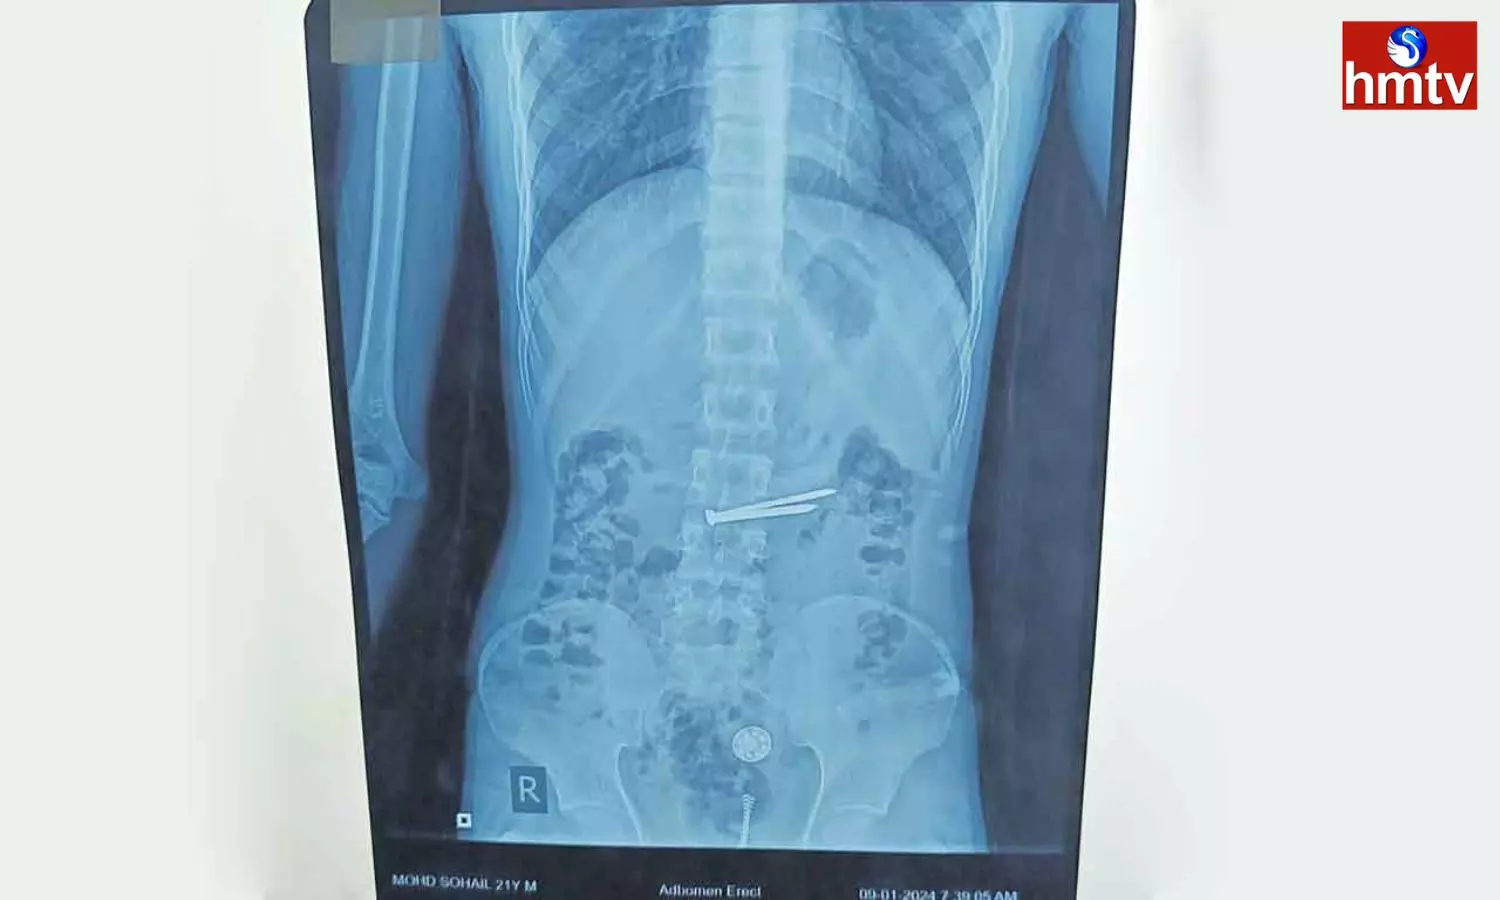

Prisoners Stomach: చంచల్గూడ జైలులో ఖైదీగా ఉన్న 21 ఏళ్ల మహమ్మద్ సొహైల్ కడుపులో ఉన్న 8 రకాల మెటల్స్ను ఉస్మానియా ఆస్పత్రి వైద్యులు విజయవంతంగా తొలగించి ప్రాణాలను కాపాడారు. జైలులో ఉన్న సొహైల్ గత కొంత కాలంగా కడుపు నొప్పితో భాధ పడుతూ ఉండటంతో జైలు అధికారులు ఉస్మానియా ఆస్పత్రికికి చికిత్స నిమిత్తం తరలించారు. జనరల్ సర్జరీ విభాగం యూనిట్-7 డాక్టర్ రోగిని పర్యవేక్షించి మెడికల్ గ్యాస్ట్రో ఎంట్రాలజీ విభాగానికి రిఫర్ చేశారు. గ్యాస్ట్రో ఎంట్రాలజీ విభాగం హెచ్ఓడీ రోగికి ఎక్స్రే తీయించగా కడుపులో మేకులు, గోర్లు, ప్లాస్టిక్ వస్తువులు, మెటల్ ఉన్నట్లు గుర్తించారు. సుమారు గంట పాటు శ్రమించి ఎండోస్కోపి సహాయంతో వాటిని తొలగించారు. ప్రస్తుతం రోగి పూర్తిగా కోలుకొని ఆరోగ్యంగా ఉన్నట్లు వైద్యులు తెలిపారు.